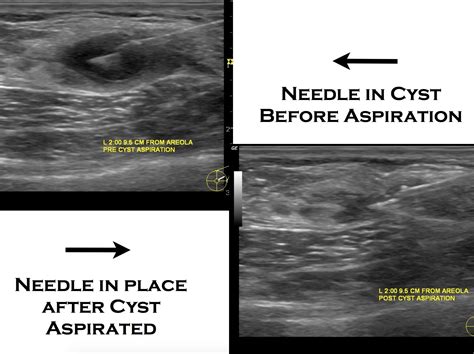

The aspiration of cysts is a minimally invasive procedure where a needle is inserted into the cyst to drain its contents. This procedure can be performed for diagnostic purposes to analyze the fluid or for therapeutic purposes to relieve symptoms. The process typically involves the following steps:

• Insertion: A fine needle is inserted into the cyst to drain the fluid.

• Drainage: The fluid is aspirated (drawn out) using a syringe.

• Needle Insertion: A fine needle attached to a syringe is inserted into the cyst. The needle is guided carefully to avoid damaging surrounding tissues.

• Fluid Aspiration: The fluid is aspirated (drawn out) using the syringe. The amount of fluid removed depends on the size and type of the cyst.